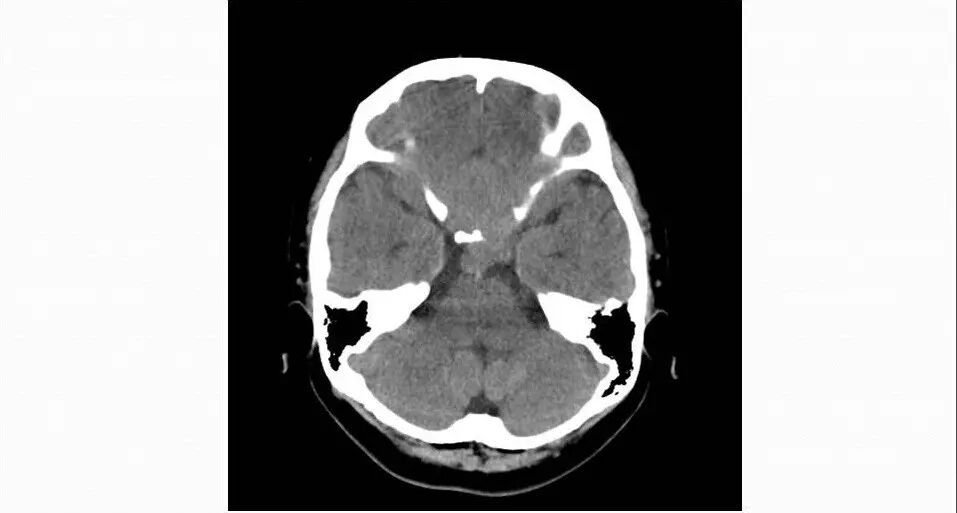

3.CT检查显示肿瘤呈等密度影,可见鞍背骨质破坏;